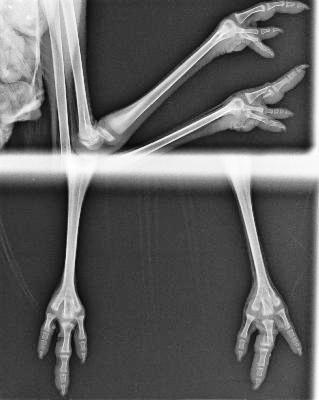

Al margen de las circunstancias que habían hecho que el animal apareciera en el jardín de una vivienda, la avutarda es una especie especialmente sensible al estrés pudiendo llegar a fallecer a causa de un manejo inadecuado, por lo que la actuación de nuestros profesionales debía realizarse con especial cuidado y minimizando el tiempo de traslado al hospital. Una vez allí, nuestros veterinarios realizaron la revisión y las pruebas necesarias mediante las cuales certificaron que nuestro joven amigo sufría una fractura en una de las falanges del dedo III de su pata izquierda, un desgarro en la zona de la cloaca además de múltiples heridas de diversa gravedad en el ala derecha, deshidratación e hipotermia. Debido a que la avutarda es un ave que pasa gran parte del tiempo caminando en busca de alimento, además de haberse recuperado del resto de patologías que presenta, la resolución de la fractura en la falange debe ser perfecta para poder liberar al animal con pleno éxito.